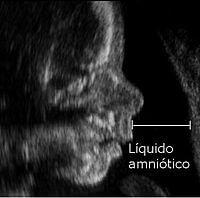

El líquido amniótico es un líquido que posee características especiales, el cual se encuentra contenido en el amnios, rodeando al embrión y posteriormente al feto. Siendo así, durante el embarazo, se pueden presentar distintas alteraciones del líquido amniótico, algunas más graves que otras. El líquido amniótico tiene las siguientes funciones:

Durante la gestación se pueden presentar alteraciones del líquido amniótico producto de múltiples causas que pueden afectar su cantidad e incluso su circulación normal, como ya se verá más adelante; es por este motivo que la ecografía es de suma importancia durante la gestación, ya que la misma es el método más efectivo para detectar alteraciones del líquido amniótico.